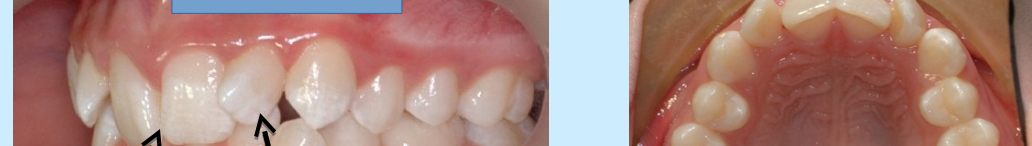

4-pseudo class 3

4-incisal interference at initial contact upon closure

-anterior functional shift of mandible to achieve posterior contact